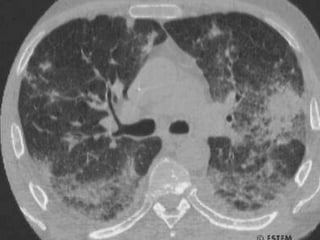

ASPERGILOSE  Agentes etiológicos: - Aspergillusflavus; Aspergillusfumigatus; Aspergillusniger; Aspergillusterreus; Aspergillusnidulans; Aspergillusrestrictus.   Doença que se localizam nos pulmões, ouvido, S.N.C., globos oculares, válvulas cardíacas e caracterizando-se por lesões granulomatoses e necrotizantes. A aspergilose pulmonar é uma das manifestações clínicas mais importantes => Aspergiloma intracavitário (bola fúngica).

ASPERGILOSE  A aspergilose raramente ocorre como doença primária em indivíduos normais, acometendo indivíduos debilitados, imunodeprimidos ou que usam drogas imunossupressoras. Aspergilosealérgica (bronquite) = granjeiros, horticultores e jardineiros. Transmissão – Inalação de poeira (propágulos) Habitat natural – plantas, solos, materiais orgânicos em geral.

ASPERGILOSE  Agentes etiológicos: -Aspergillusflavus; Aspergillusfumigatus; Aspergillusniger; Aspergillusterreus; Aspergillusnidulans; Aspergillusrestrictus.   Doença que se localizam nos pulmões, ouvido, S.N.C., globos oculares, válvulas cardíacas e caracterizando-se por lesões granulomatoses e necrotizantes. A aspergilose pulmonar é uma das manifestações clínicas mais importantes => Aspergiloma intracavitário (bola fúngica).

ASPERGILOSE  A aspergiloseraramente ocorre como doença primária em indivíduos normais, acometendo indivíduos debilitados, imunodeprimidos ou que usam drogas imunossupressoras. Aspergilosealérgica (bronquite) = granjeiros, horticultores e jardineiros. Transmissão – Inalação de poeira (propágulos) Habitat natural – plantas, solos, materiais orgânicos em geral.